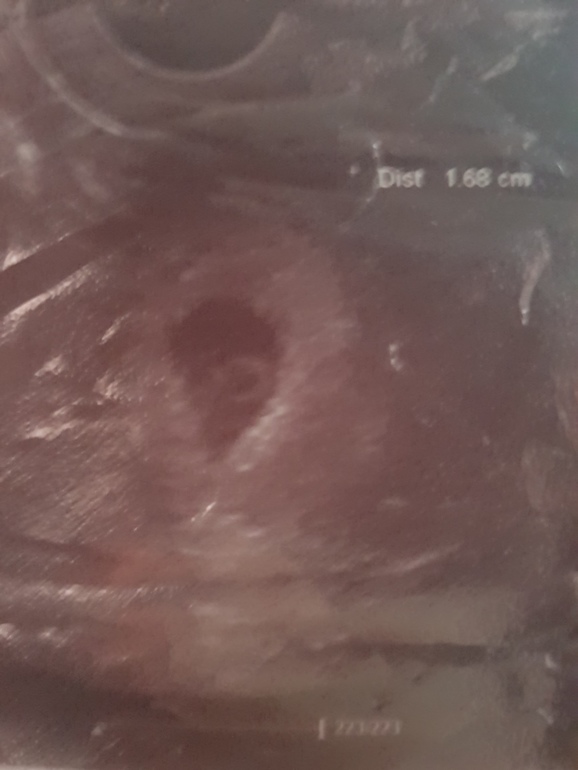

узи на 31дпп

Сохранение ЭКО-беременностиДевочки, все хорошо) Ре сказала кор выделения могут быть от крайнона, добавила дюфастон+1 . На узи пя 16,8 мм, жм д 3мм, ктр 3-4 мм. Серцебиение есть, но она сказала не очень четкое. Следующее узи 19.10. Спасибо всем за поддержку🙏🙏🙏